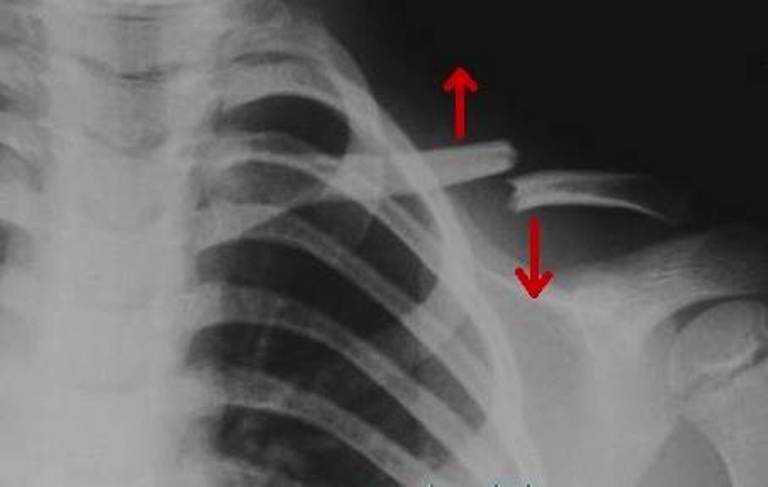

• Рентген ключицы. Фундаментальные исследования патологии костей и суставов. На снимках видны линии перелома, смещения суставных поверхностей при вывихах, нарушения структуры и формы костей при опухолях, остеомиелит, деформирующий остит, деформации, изменение конфигурации суставов при артрозах и псориатических артритах.

Рентгенография. Перелом ключицы.